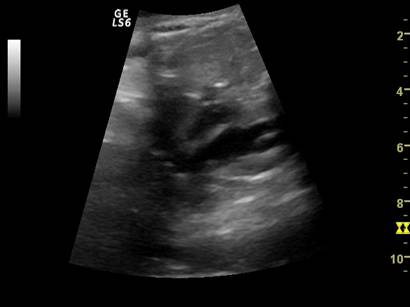

Fig. nr. 273. Dilatatie pielocaliceala renala fetala, unilaterala, la 16 sapt.( sageata)